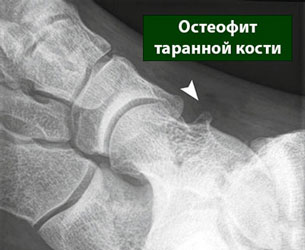

- Массивные остеофиты

массивные остеофиты остеофит таранной кости

Объемные разрастания, способные даже изменить конфигурацию сустава, в основном являются следствием воздействия на организм патологий опухолевой природы.